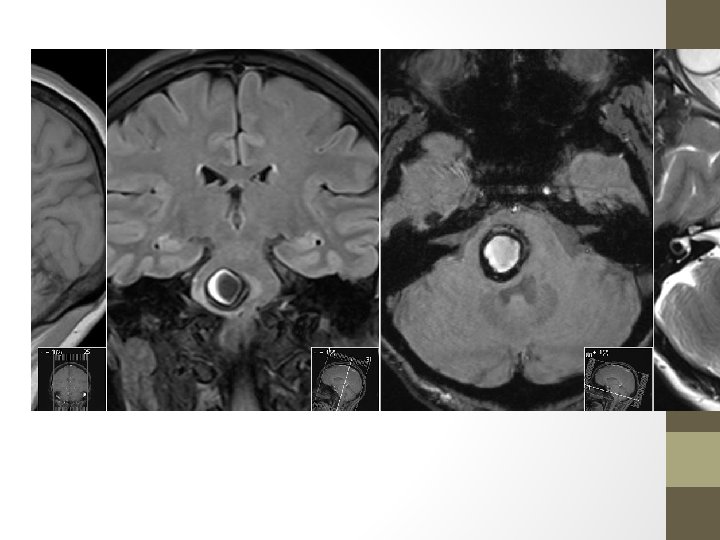

Cavernous Malformations • Mostly single lesions • Multiple lesions may be familial and screening of family members may be indicated (familial multiple cavernous malformation syndrome) • Along with capillary telangiectasias, are commonly seen following cerebral radiotherapy • Mostly asymptomatic- or hemorrhage and seizures • Composed of a "mulberry-like" cluster of dilated thin-walled capillaries, with surrounding hemosiderin. (Unlike AVMs, there is no normal brain between the interstices of these lesions. ) • %80 supratentorial • Characteristic popcorn appearance in MRI • Symptomatic lesions should, when possible, be resected and complete resection is curative